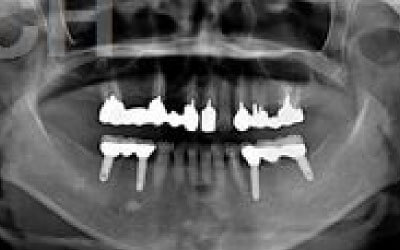

CTでは、骨や歯の状態を3Dで確認でき、正確な距離の測定も行えます。

骨の厚さや傾き、神経の位置などを事前にしっかりと測定することで、安全にインプラントを行うことができます。